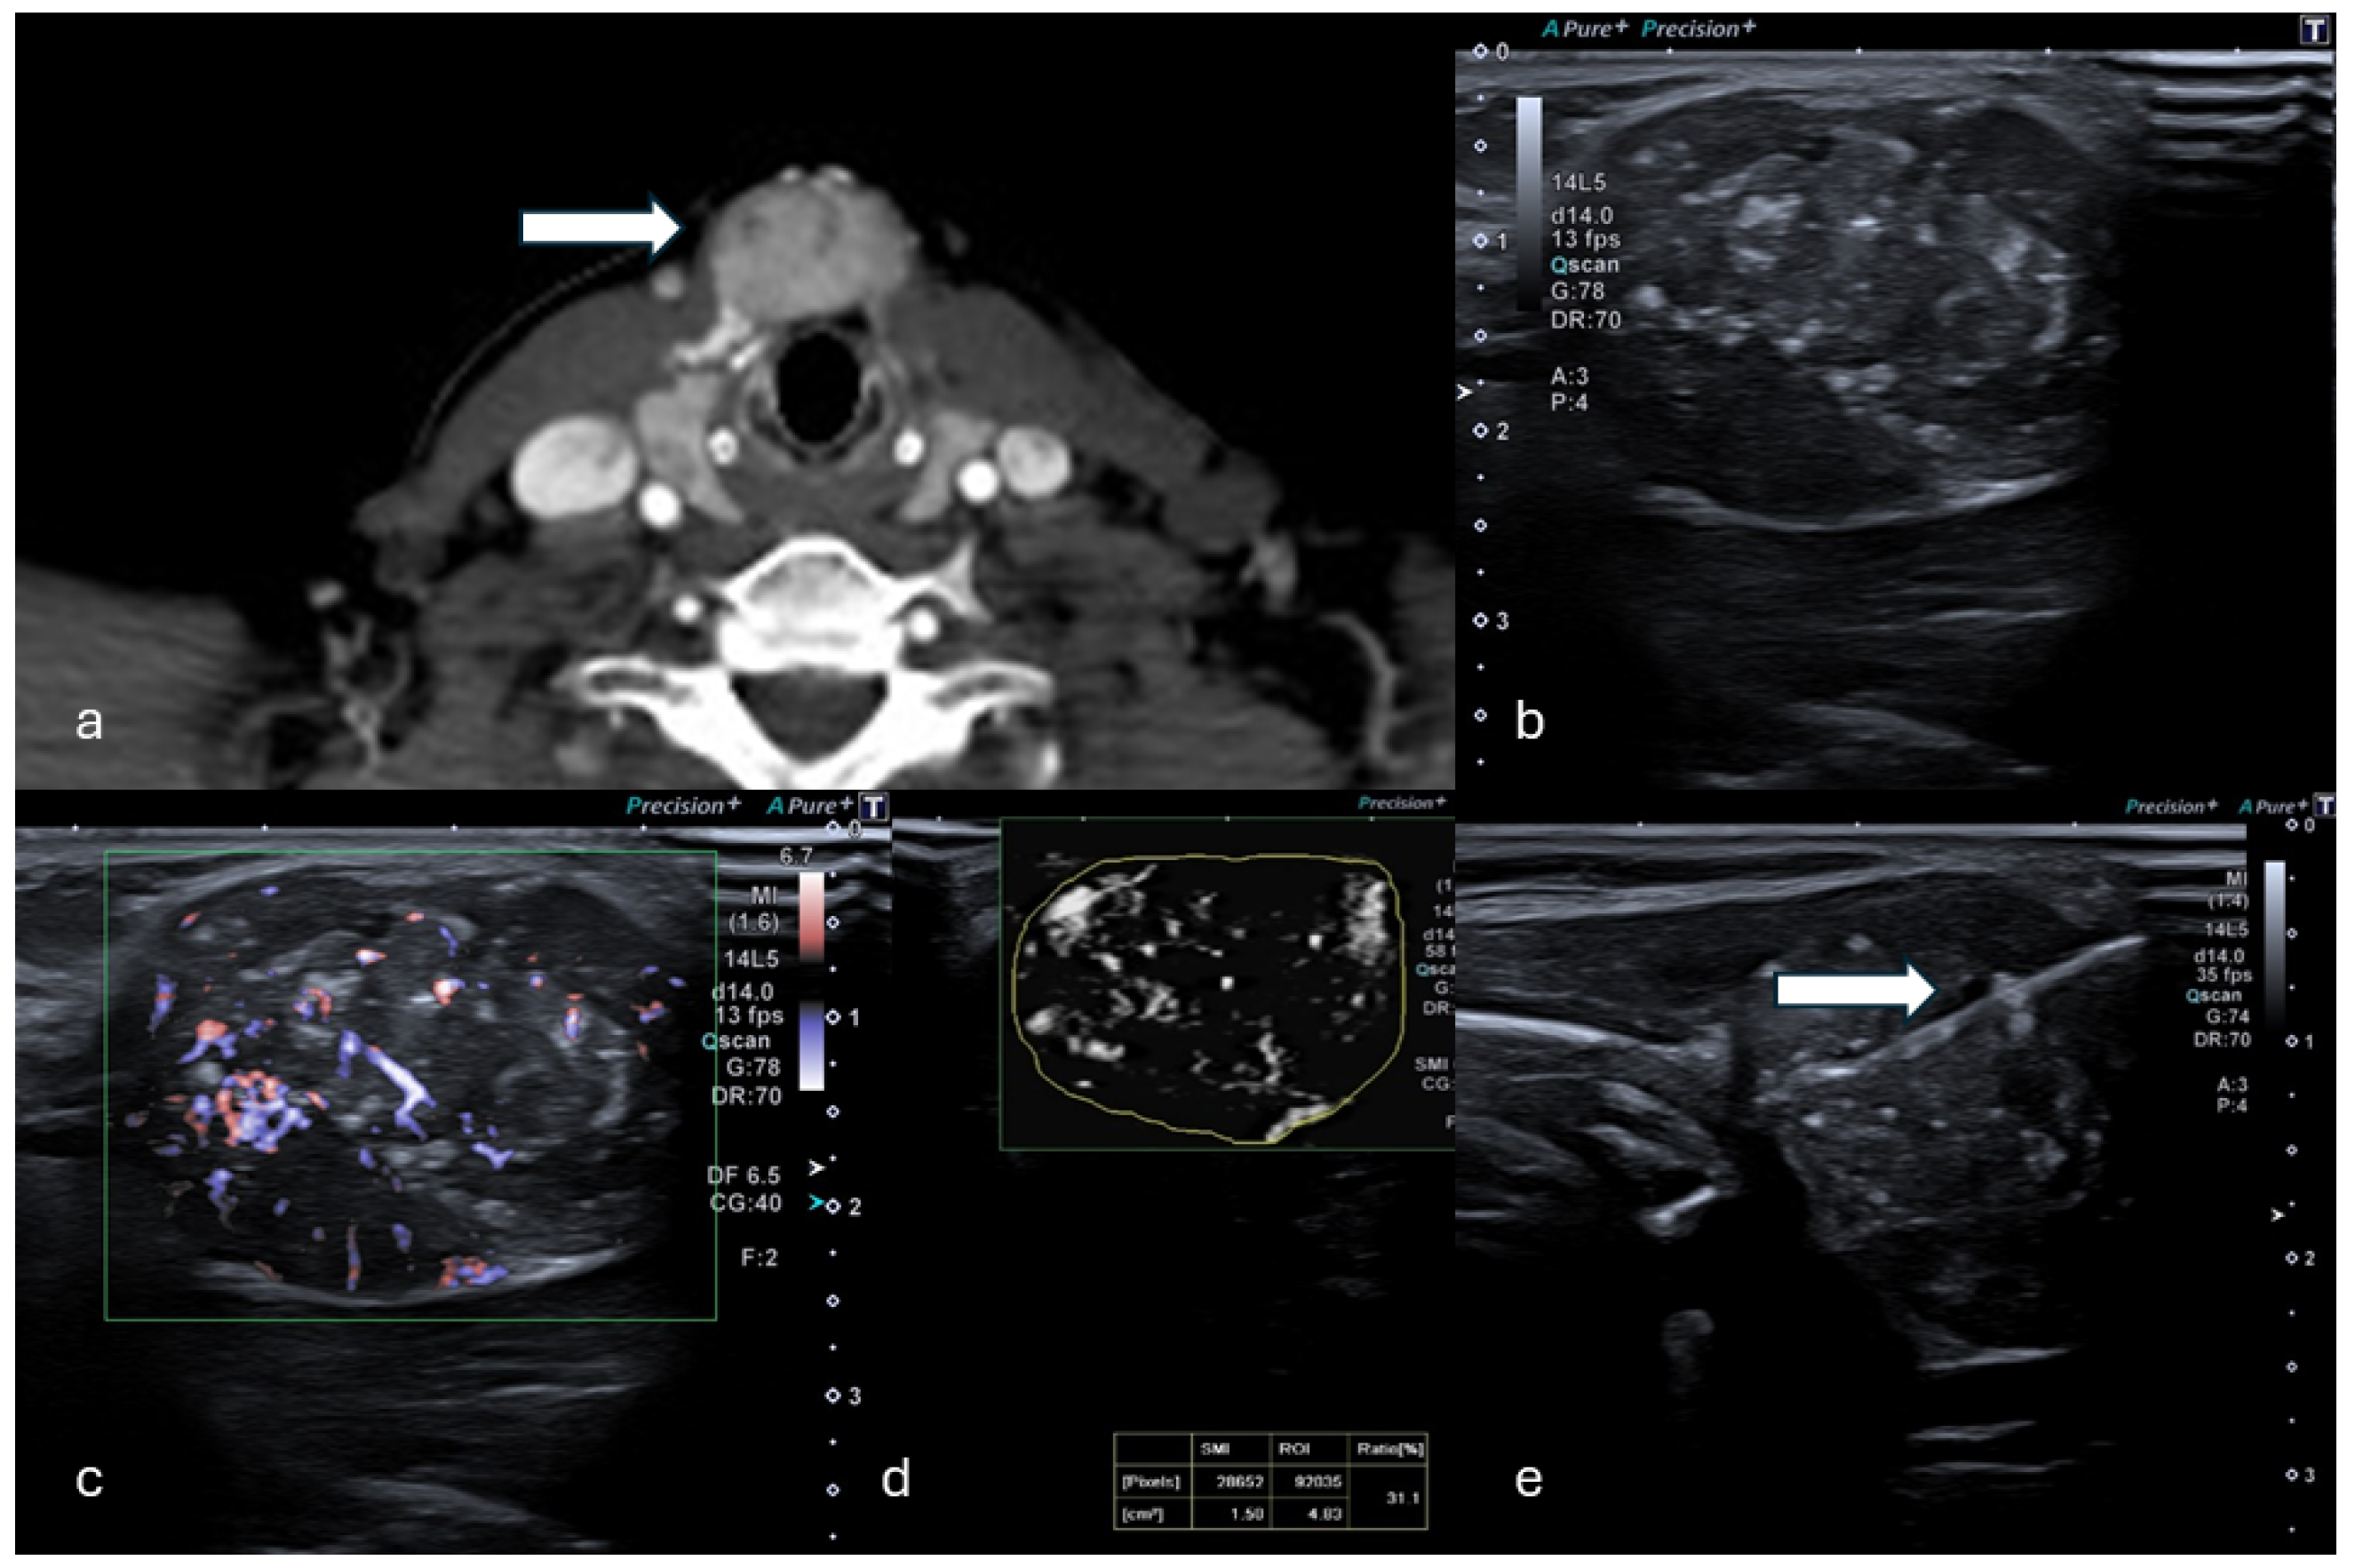

Figure 2.

(a) Axial CT in venous phase shows a hyperdense, vascularized 24 mm solid lesion of the thyroid (white arrow) in a patient who presented with a palpable mass. (b,c) B-mode US showed a dishomogeneous hypo-isoechoic lesion. (d) mSMI and VI analysis providing a value of 31.1%. (e) Percutaneous biopsy using an 18G needle (white arrow). (Histological examination reported a papillary thyroid carcinoma.).